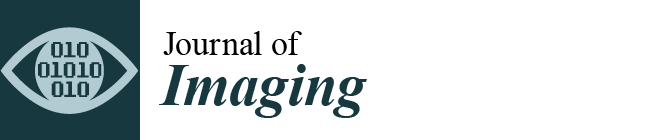

2. Reconstruction Methods

2.1. Embedded T Model

2.2. Compressed Sensing Reference Methods